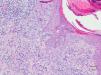

HistopathologyA punch biopsy of one lesion showed an inflammatory infiltrate in the superficial dermis containing histiocytes, several multinucleated giant cells, and lymphocytes expressing T and B immunohistochemical markers, without significant atypia or the presence of lymphocytes in the epidermis. Collagen degeneration was present, with a discrete mucin deposit. Elimination of a material consistent with degenerated collagen through epidermal interruptions was observed in certain areas of the lesion (hematoxylin-eosin, original magnification ×100) (Fig. 2).